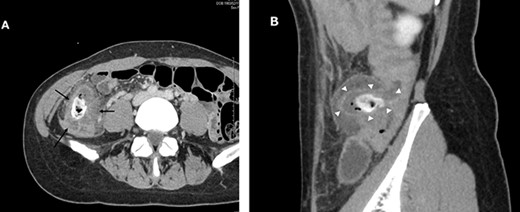

A 38-year-old woman presented with lower right abdominal pain of 3 days duration before the consultation. She had a history of left ovarian cystectomy and no history of medication use or allergies. She was 172-cm tall and weighed 59.0 kg. On examination, there was right lower abdominal pain with no rebound tenderness. The white blood cell count was 13 600 /μl, and the C-reactive protein was 3.8 mg/dl. Contrast-enhanced computed tomography (CT) revealed a 4-cm cecal diverticulum with inflammation and a fecalith (Fig. 1). An abscess penetrated through the mesenteric side and was localized in the mesentery. The diagnosis was cecal colonic diverticulitis and classified as Hinchey II. The abdominal symptoms were localized; hence, the patient was treated with antibiotics. From Day 1 of hospitalization, she was on nil per oral and administered CMZ at 3 g/day. On hospitalization Day 3, the right lower abdominal pain improved, and contrast-enhanced CT imaging was performed. The cecal colonic diverticulitis improved, and the fecaliths migrated to the transverse colon (Fig. 2). Moreover, the inflammatory reaction improved. In a multidisciplinary meeting, we discussed that the patient should undergo a detailed examination, including colonoscopy, and elective surgery after readmission. However, we suggested that surgical treatment should be performed as early as possible after considering the risk of early recurrence and bleeding. The patient wished to undergo minimally invasive surgery; thus, we performed an immediate ileocolectomy and lymphadenectomy using SILS as we did not rule out the likelihood of malignant disease.

Abdominal and pelvic CT with intravenous contrast at the time of consultation. Axial image (A) demonstrated cecal colon diverticulum (black arrows) and sagittal image (B) demonstrated thickening and mural edema of the diverticulum (white arrowheads), indicating inflammation.